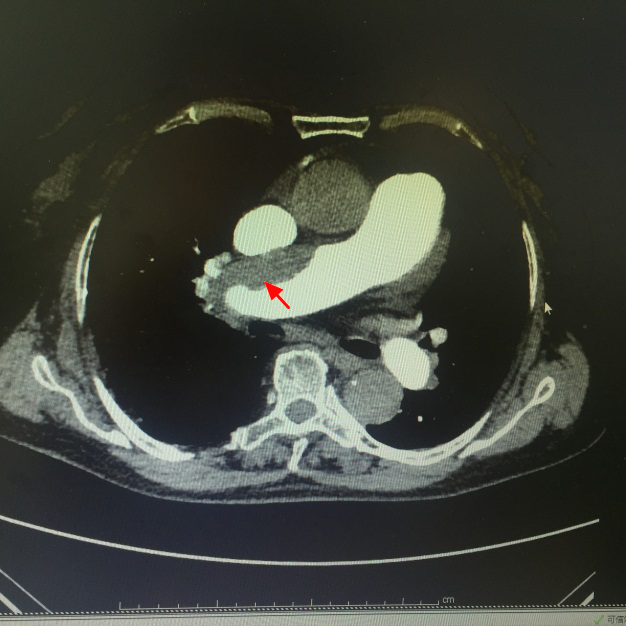

回顾患者病史:房颤病史多年,水肿10月,难道下肢血栓形成引起?遂完善双下肢超声未见明显异常。但完成心脏超声惊奇发现:肺动脉高压。根据肺动脉高压这个线索,彭教授团队开始怀疑是否存在肺栓塞?(患者存在活动后呼吸困难伴干咳,双下肢严重水肿,但无胸痛、无咯血等肺栓塞典型临床表现),于是便完善肺动脉CTA,检查结果提示:右肺动脉干栓塞。找清病因后,对症予以抗凝、利尿等治疗后,患者双下肢水肿明显消退,患者近期已出院。

(红色剪头提示:肺栓塞部位)